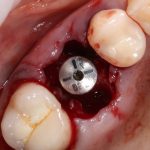

Когда мы говорим об ультракоротких (7 мм и менее) имплантах, то в первую очередь на ум приходит Bicon:

В далеком 1986 году американский профессор V. Morgan разработал концепцию субкрестальных коротких имплантов с фрикционной платформой. Последнее означает, что ортопедический интерфейс не имеет каких-либо антиротационных элементов (шестигранника и т. д.), а фиксация супраструктуры, коронки или абатмента, происходит путём «заклинивания»:

В этом есть, безусловно, революционность имплантов Bicon, их отличие от других современных имплантационных систем, в этом их главное преимущество и главный недостаток.